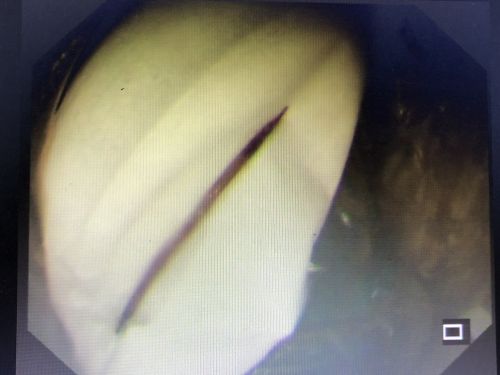

胃镜下取出一根完整的牙签。

听说胃镜下取牙签,不排除出现胃穿孔的情况,家人决定将老人转往长沙的大捷克论坛 ,于是在9月23日住进捷克论坛 胃肠外科病房。刘祺主任医师与消化内科吴明浩主任医师凭借胆大心细和高超技术,成功在胃镜下取出一根长约6厘米的完整牙签。

“牙签不仅把胃壁戳了两个洞,还穿过胃壁戳伤胰腺,导致胰腺周围感染、脓肿”,刘祺表示,如果不及时取出牙签,将导致胰腺感染、坏死、出血,并威胁周边大血管,患者将有生命危险。